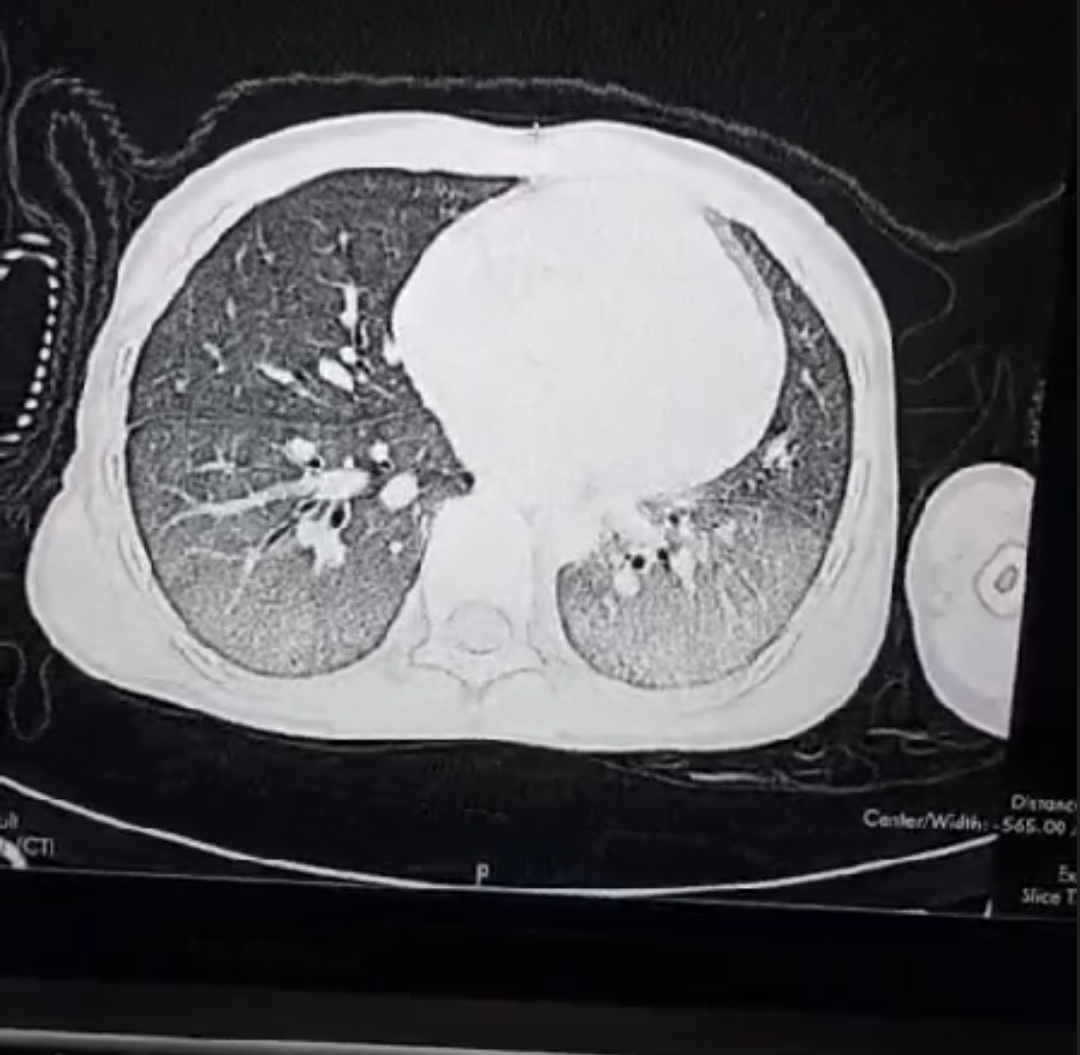

Both of them were rushed to our ward. Both of them had CT scans that showed the extent of their lung damage. Both of them fought, and we fought with them. But in cases like these, our fight feels so unfair—because the poison is almost always stronger than medicine.

Child A

Child B